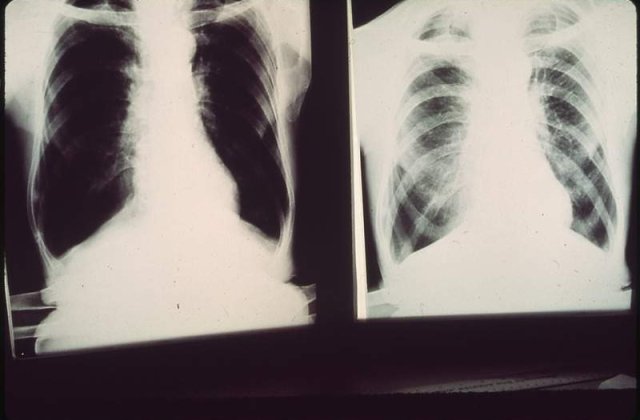

Directorul Directiei de Sanatate Publica din Constanta, dr. Constantin Dina, a declarat, miercuri, ca cele doua cazuri au fost confirmate, dar au existat si trei suspiciuni in randul colegilor elevului, care nu s-au confirmat.

"Directia de Sanatate a inceput o actiune de screening a elevilor si cadrelor didactice de la Liceul Traian prin testare tip IDR. Este vorba despre aproximativ 150 de elevi, dar si de cadrele didactice din liceu care au intrat in contact cu cei doi bolnavi”, a mai precizat Constantin Dina.